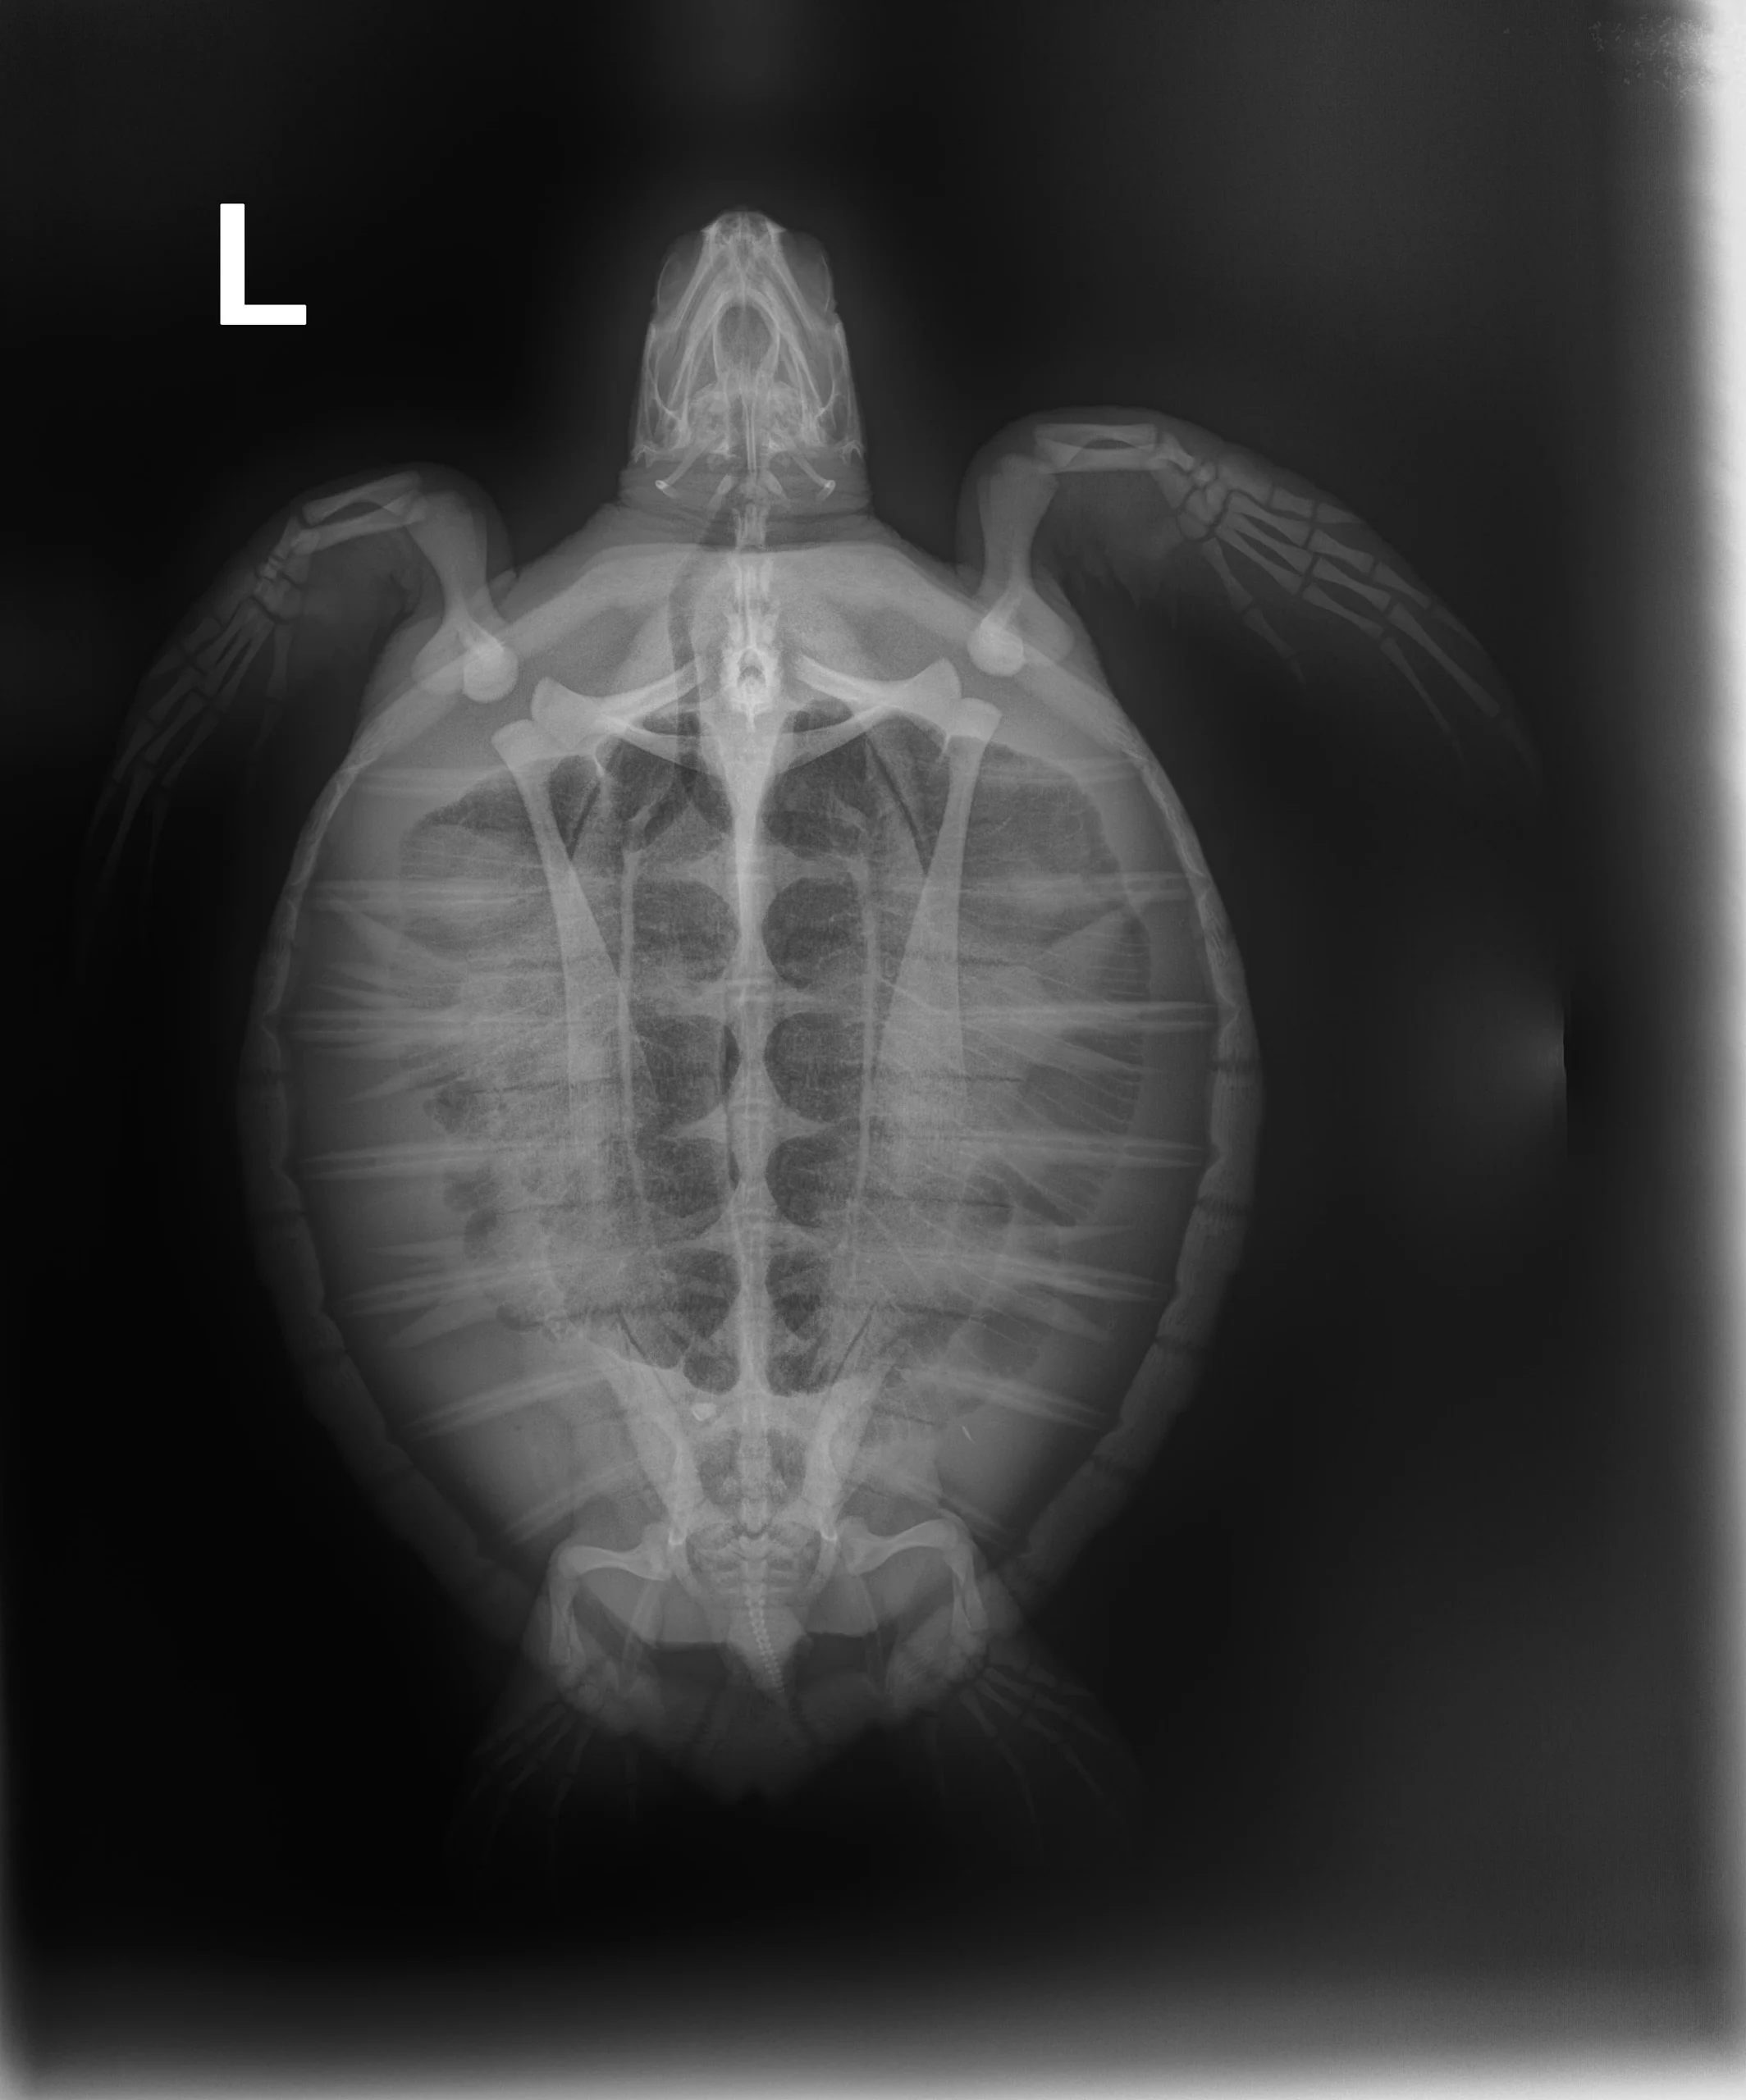

3.7 lbs./ 1.7kg juvenile, Atlantic Green

Moderate plastron abrasions, minor carapace abrasions

In-house PCV = 25%, TP = 2.4 g/dl, Glucose = 86. Started on Ceftaz (broad spectrum antibiotic), Vit B (vitamin complex shot), and Normosol (for fluids).